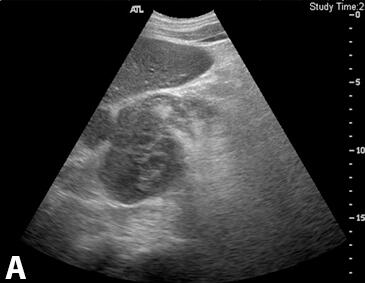

每年,成千名加拿大前列腺癌男性患者都会接受活组织检查来帮助医生更好地理解患者的病情进展以及疾病的特性,进行活组织检查能够提供关键的信息,然而癌症研究者John Lewis深知要求任何一名患者进行检查非常困难。他认为,目前获取病情进展的最佳方法就是进行活检,这种方法就是利用12根针推入患处取样进行检测,低度前列腺癌患者通常并不会进行疗法治疗,而是会选择实时监测疾病的进展,但监测通常也需要每年进行活检,很多人更愿意采用手术来替代活检。 近日,刊登在国际杂志Cancer Research上的一项研究报告中,来自埃博塔大学的研究人员希望通过一种相对无痛的方法来对患者的检查进行改善,文章中研究者利用一种聚焦超声(Focused Ultrasound)技术联合纳米滴来对患者血液中的癌症标志物进行增强化的检测,在肿瘤中采用该技术就能够促进细胞外的囊泡释放到血液中,从而就能够对大量遗传物质进行检测来对较小样本的血液进行检测。